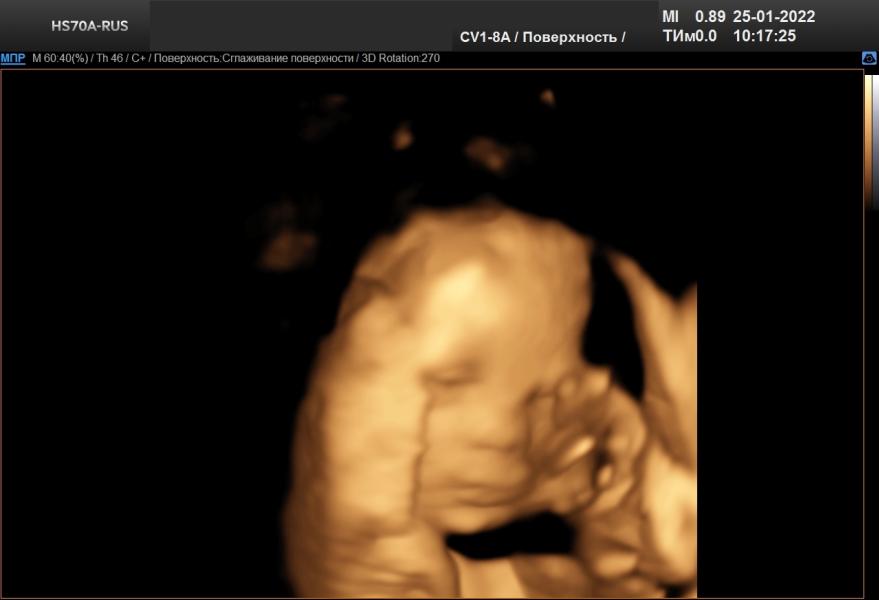

Поздравляю всех Татьян, Танечек, Танюшек с днём ангела. Ну а саму себя ещё и с началом декрета💃💃💃Дождалась🤣🤣🤣И начался он прекрасно, с утра ездила на УЗИ, увидела моего маленького мальчишку🧒🧒🧒Всё с ним хорошо, соответствует по размерам 31.1 неделям, весит 1713 грамм. Улыбался, открывал глазки💙💙💙Мы ждём тебя родной наш сынок❤❤⚘

Какой красивенький 😍мне показалось или на Вас похож ?